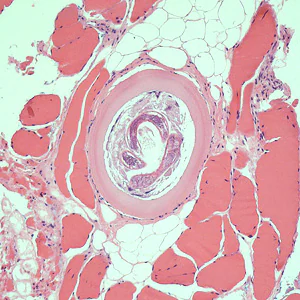

A hunter prepared dried jerky from fresh bear meat and provided some to a group of friends. Most developed moderate to severe abdominal pain, nausea, and fatigue within 48 hours. Some of the bear meat was submitted for laboratory testing. Images of stained histological sections of bear meat were sent to the DPDx Team for confirmation of parasites. Figures A and C were taken at 200x magnification; Figures B, D, and E were taken at 400x magnification. What is your diagnosis? Based on what criteria?

Figure A